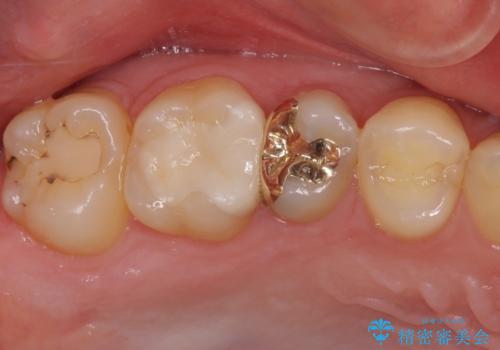

セラミックインレー 痛む歯の治療

奥歯の深い虫歯をオールセラミックで治療